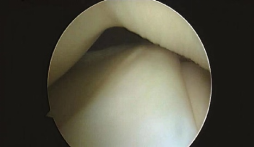

盘状半月板的MRI诊断方法

图片来源:doi:10.1136/jisakos-2017-000162.

MRI诊断方法:

(A)质子密度脂肪饱和序列中,连续3个5mm厚的矢状面前后角相连。

(B) T2加权冠状面外侧半月板宽度为胫骨总宽度的20%(黄色箭头)。

(C)半月板轴位片显示外侧半月板明显的盘状形态(黄色箭头),覆盖胫骨外侧平台的>80%。